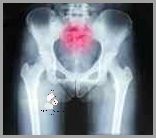

Ból kości ogonowej bez urazu może być spowodowany przez wiele czynników. Najczęstszymi przyczynami są zwyrodnienia stawów, przepuklina dysku, choroby zapalne stawów lub nerwoból. Ból może być także spowodowany urazem, na przykład w wyniku upadku.

Ból kości ogonowej bez urazu jest częstym zjawiskiem, zwłaszcza u osób w wieku powyżej 40 lat. Jest to wynikiem wzrostu zmian zwyrodnieniowych w układzie mięśniowo-szkieletowym. Dolegliwości bólowe mogą nasilać się wraz ze wzrostem aktywności fizycznej. W celu złagodzenia dolegliwości bólowych, zaleca się leczenie przeciwzapalne, fizykoterapię oraz dostosowanie aktywności fizycznej do indywidualnych predyspozycji. Dieta powinna być bogata w składniki odżywcze, a przede wszystkim w wapń i witaminę D.